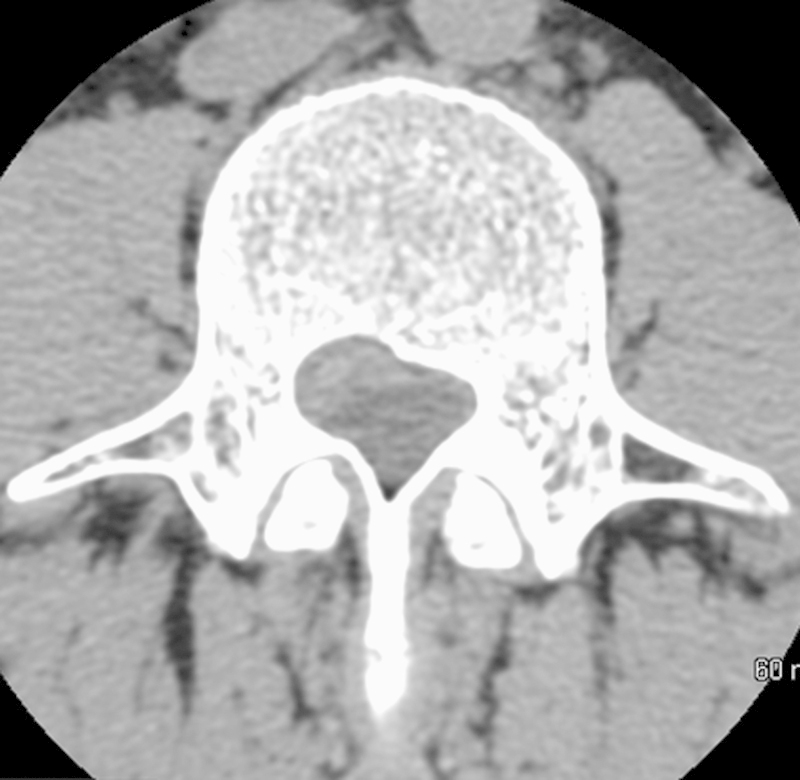

研究设计、个案报告及文献回顾。目的报告一例成功应用显微手术治疗腰椎间盘囊肿的病例,并对目前有关腰椎间盘囊肿诊断和治疗的文献进行综述。方法男性患者,43岁,表现为严重的背部疼痛,放射至右腿,并伴有右侧L3和L4皮节的感觉异常。腰椎磁共振成像显示在L3-L4椎间盘水平有椎管内、硬膜外占位性病变,导致神经结构受压。手术切除病变,诊断为腰椎间盘囊肿。术后症状改善,无并发症出院。对截至2014年2月发表的相关文章进行系统综述。检索关键文章以确定描述腰椎间盘囊肿的诊断和治疗方式以及显微手术与内窥镜治疗的有效性和安全性的研究。结论腰椎间盘囊肿是引起腰痛和神经根病的罕见原因。报告的病例很少;然而,关于它们的自然历史的结论性信息是不可获得的,最好的治疗方式仍然存在争议。我们认为腰椎间盘囊肿具有特殊的放射学和解剖学特征,应在腰痛和神经根病的罕见病因中进行鉴别诊断。

Study Design Case Report and review of the literature. Objective The objective of the article is to report an illustrative case successfully treated by microsurgery and to review the literature on the current evidence on diagnosis and management of lumbar discal cysts. Methods A 43-year-old male patient presented with severe back pain, radiating down to the right leg, as well as with paraesthesias in the right L3 and L4 dermatomes. Magnetic resonance imaging of the lumbar spine revealed an intraspinal, extradural space-occupying lesion at the L3-L4 disc level, causing compression of the neural structures. The lesion was surgically removed and a diagnosis of lumbar discal cyst was made. Postoperatively, symptoms improved and the patient was discharged with no complications. A systematic review of pertinent articles published up to February 2014 was performed. Key articles were searched to identify studies describing the diagnosis and management modalities of lumbar discal cysts and the comparative effectiveness and safety of microsurgery versus endoscopic treatment. Conclusions Discal cysts are rare causes of low back pain and radiculopathy. Few cases have been reported; however, conclusive information about their natural history is not available and the best mode of treatment remains controversial. We submit that lumbar intervertebral disc cysts, with their peculiar radiological and anatomic features, should be considered in the differential diagnosis among rare causes of low back pain and radiculopathy.